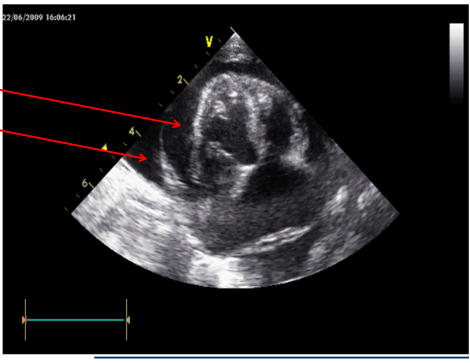

What does Felix’s ultrasounds show?

Felix was treated for congestive cardiac failure secondary to myocardial disease as detailed on the next slide – can you see the rationale for this?

Clinical signs of HCF